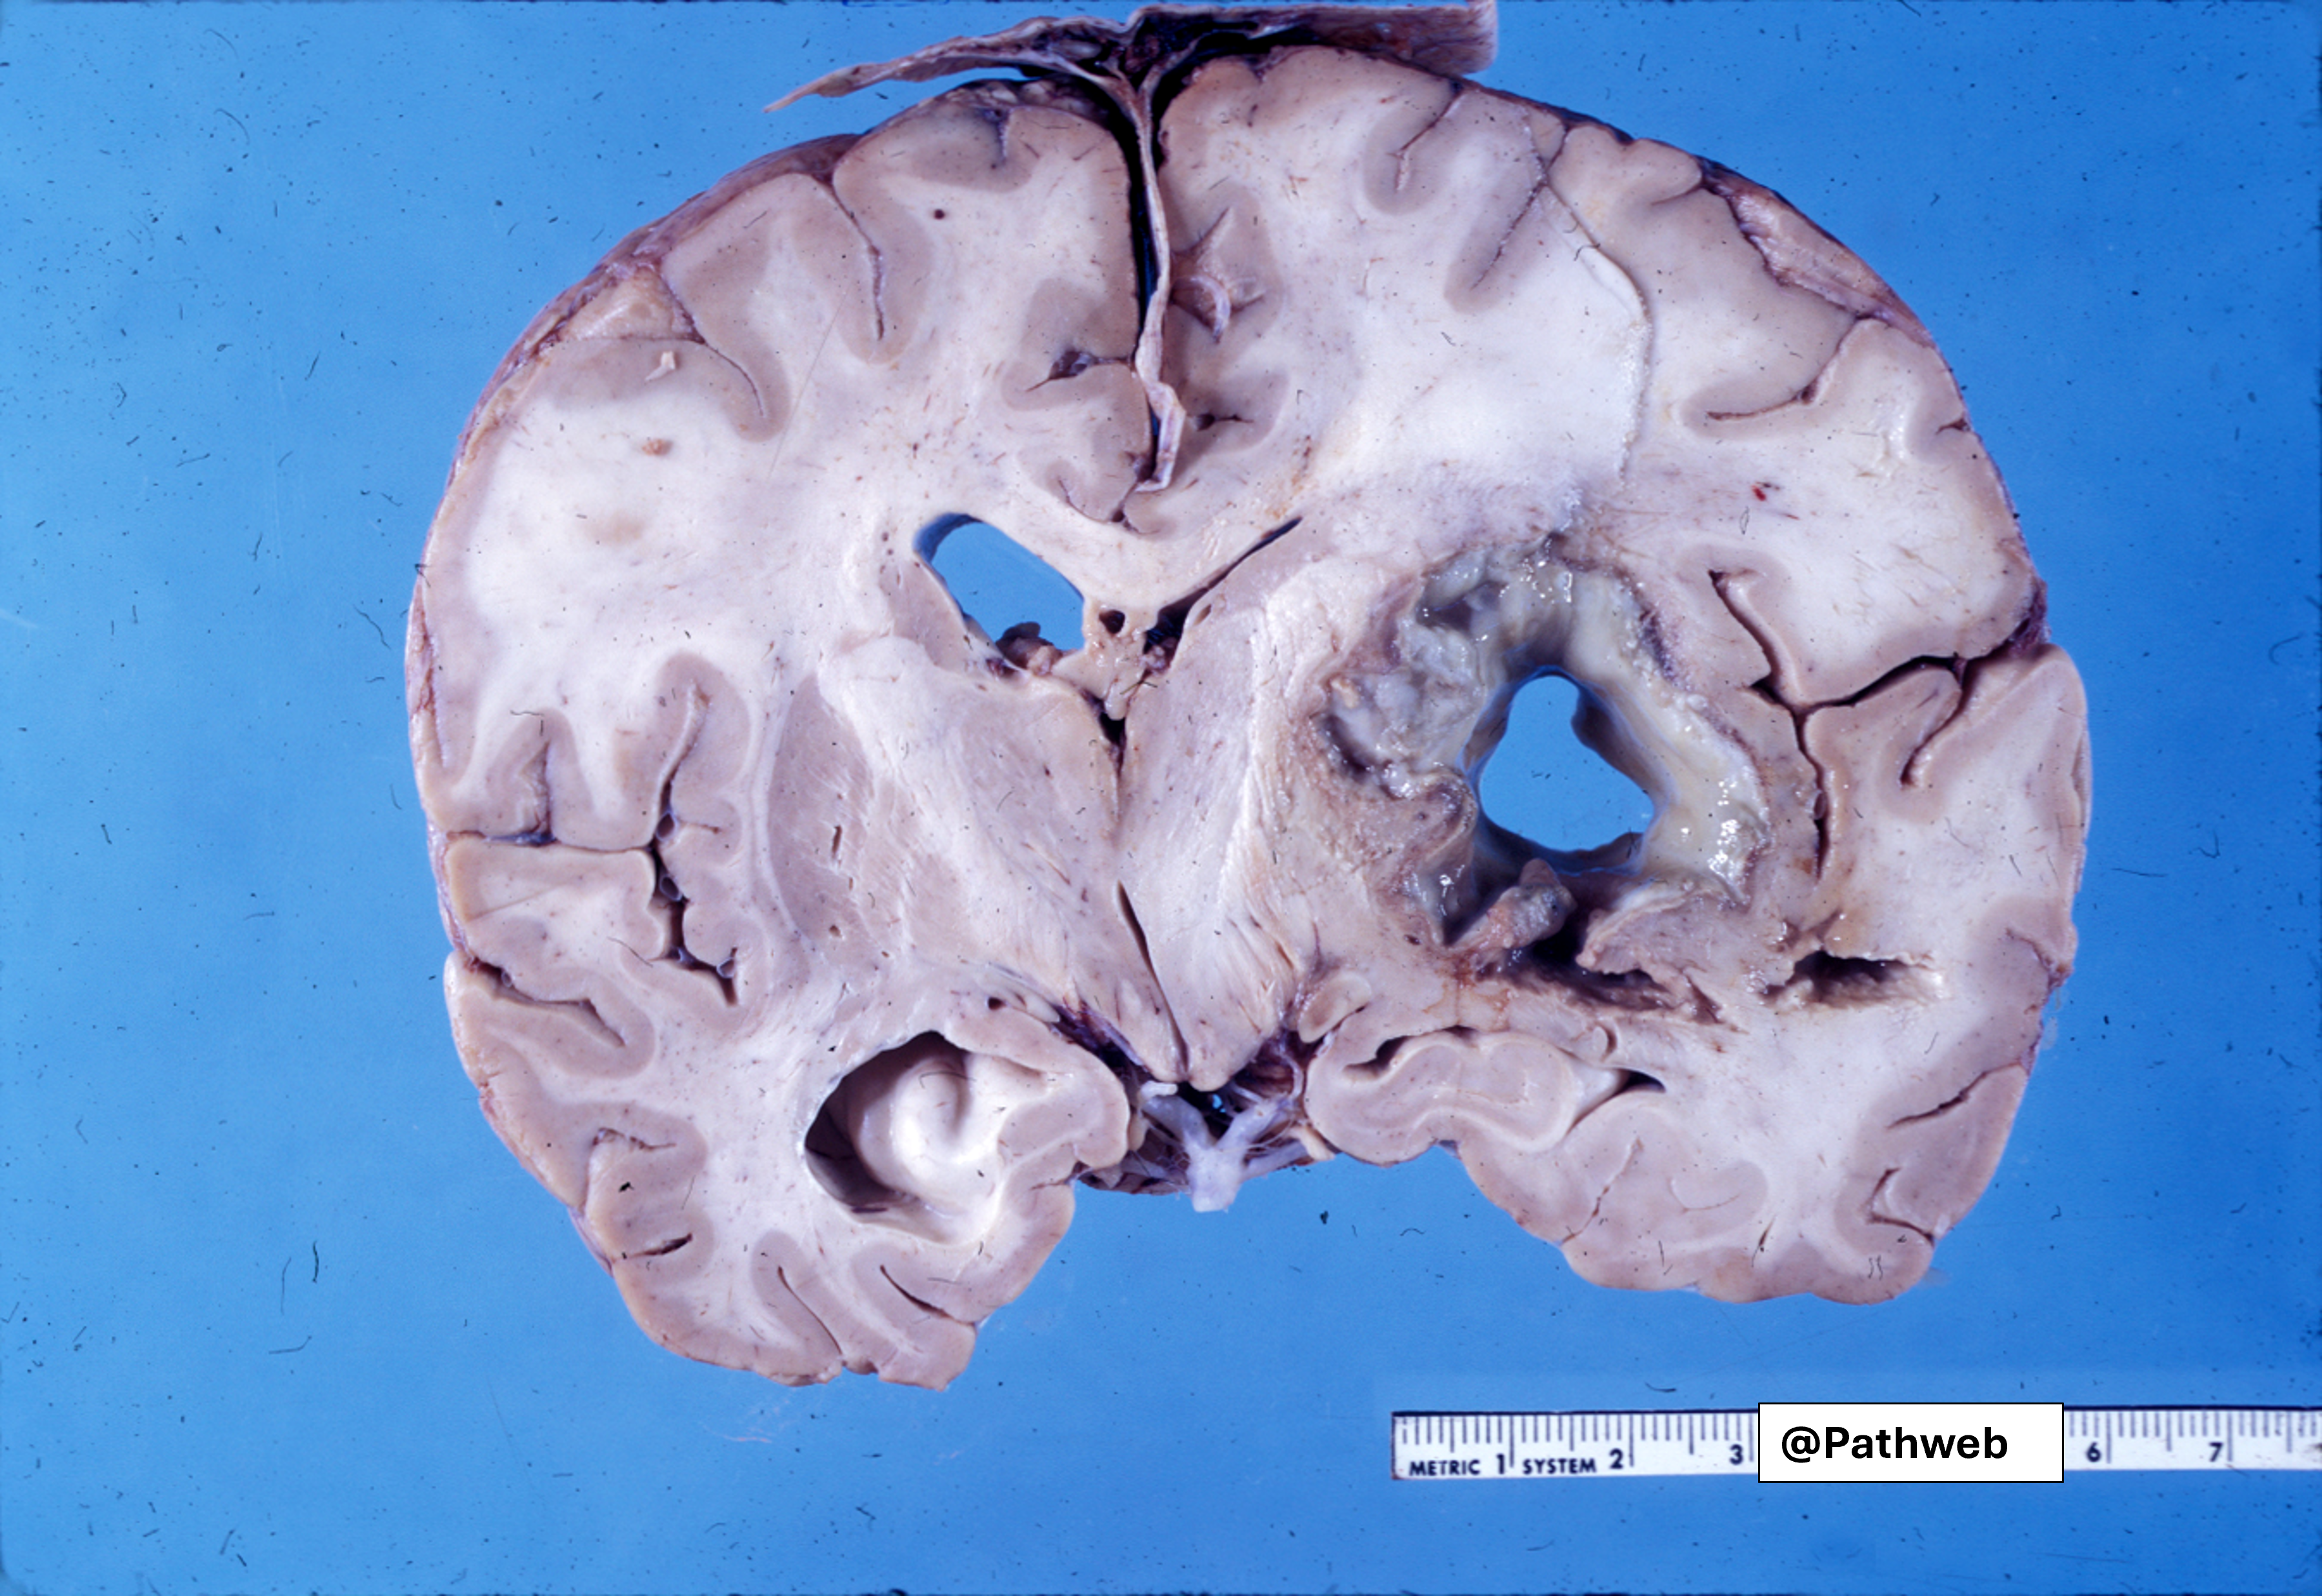

45 year old man with focal neurologic deficits, headache and fever for several weeks.

Cerebrospinal fluid (CSF) analysis showed increase in white cell count, elevated protein concentration but normal glucose content.

The affected cerebral hemisphere is swollen. Cut surface shows a large well-defined cavity (due to liquefactive necrosis and suppuration) lined by a layer of creamy fibrinopurulent exudate resting on a collagenous capsule.

There is compression but no rupture into the lateral ventricle.